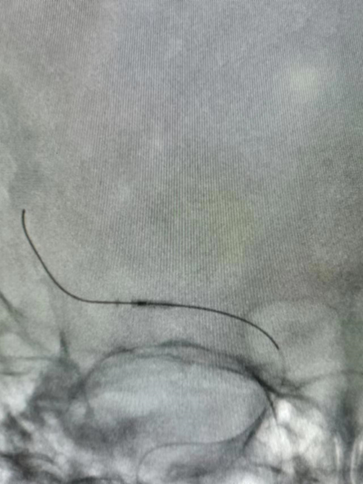

Guiding到位,导丝通过病变。

导丝怎么扩【载药时代 球扩天下】NOVA DES®颅内药物洗脱支架在大脑中动脉重度狭窄的应用二例!_https://www.jmylbn.com_新闻资讯_第24张